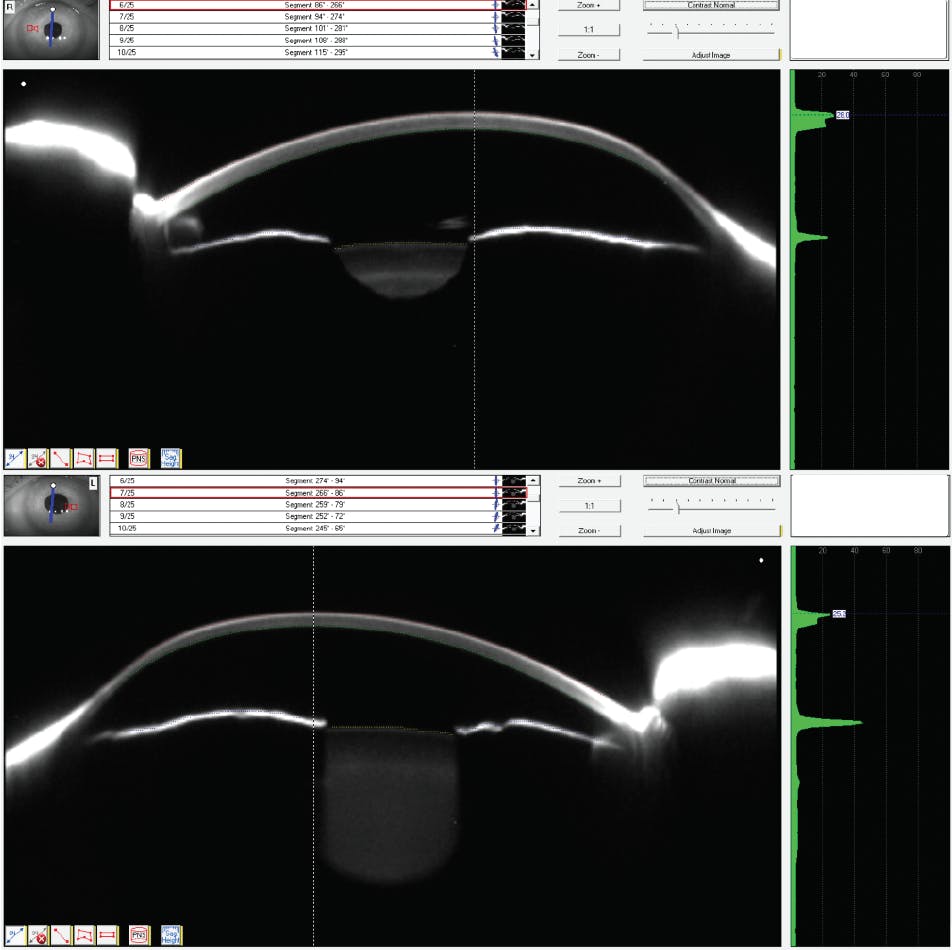

Entering acuity with the current soft lenses was OD 20/200, OS 20/100. The soft lenses were well centered with good coverage. There was notable vascularization of 1.0 mm of both corneas inferiorly from the 8 o’clock to 4 o’clock position. Her current spectacles were OD -2.00-8.25 x 091 and OS -4.50-7.50 x 088. Retinoscopy showed OD -4.50-9.00 x 090 20/70+ and OS -4.50-12.00 x 090 20/60+. She was unable to respond to subjective refraction. Corneal topography and corneal tomography (Figures 1 and 2) are seen below.

In Figures 1 and 2, it can also be seen that the central cornea on both the right eye and the left eye show the pachymetry apex at 627 µ and 555 µ, respectively. The pachymetry readings that show significant thinning are in an arc near the inferior limbus, with values in the 300 µ range, and a greater area affected on the right eye.

The overall distortion to this pair of corneas, displacement of the corneal apex, and the area of greatest thinning can be visualized much better on the actual photographic Scheimpflug images in Figure 3. The remainder of the examination clinical data are noncontributory.